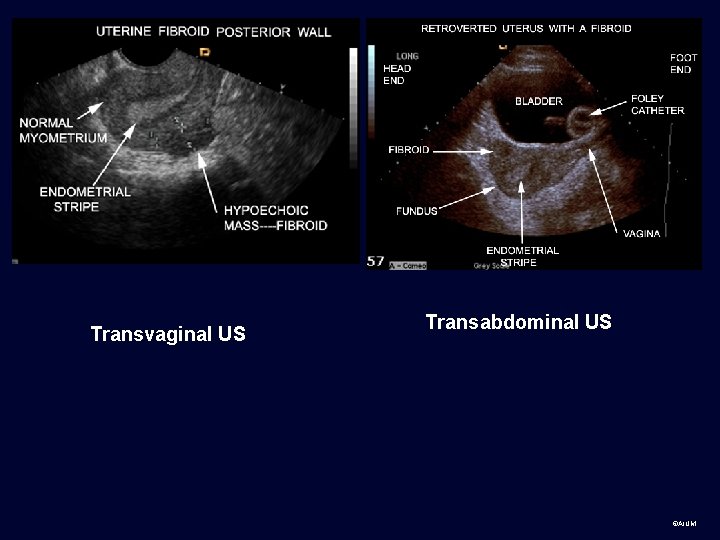

Transvaginal US Transabdominal US ©AIUM

Use all the information from the labeling that you are given to orient yourself to anatomy Long= longitudinal, usually sagittal relative to body. Convention: patient’s head to left of screen. Trans=transverse, usually axial relative to body. Convention: patient’s right side to left of screen. ©AIUM